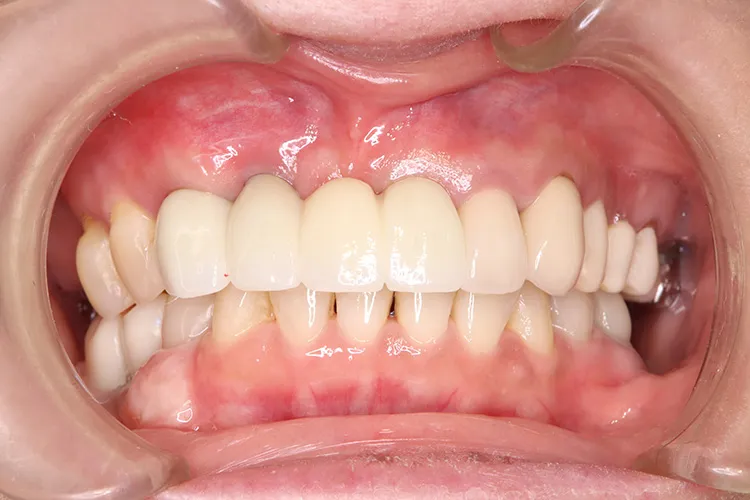

前歯の古いブリッジが脱離し、土台となっていた3本の歯も傷みがはげしく再度のブリッジ治療が不可能な状態でした。前歯ということで欠損を放置できないため、抜歯と同時にインプラントを3本埋入し即日で仮歯までいれました。治療期間中、見た目を気にすることなくオペから4ヶ月で最終のジルコニア4本ブリッジを装着し治療完了しました。抜歯即時埋入は術後の痛みもほとんどなく、治療期間の短縮や患者様の負担軽減などメリットの大きい治療法です。